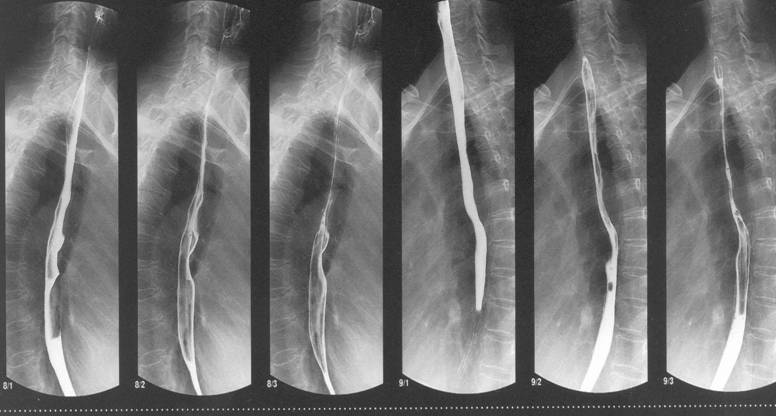

Для подтверждения диагноза необходим целый комплекс исследований, при участии сразу нескольких специалистов. Первое, с чего начинается диагностика – опрос и осмотр маленького пациента. При подтверждении предварительного диагноза, деткам назначают проведение контрастного рентгенологического исследования. В качестве контраста используют барий. Этот визуальный метод исследования позволяет обнаружить возможные опухоли, наличие язв глотки и пищевода.